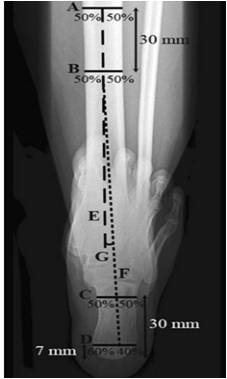

| 后足长轴位 1. 确定胫骨长轴E 2. 确定跟骨长轴F – 距跟骨最低处7mm处做水平线C,分为3:2 – 距跟骨最低处30mm处做水平线D:分为1:1   |

| Saltzman 位 1. 确定胫骨长轴E 2. 确定跟骨长轴F – 距跟骨最低处7mm处做水平线C,分为3:2 – 距跟骨最低处20mm处做水平线D:分为1:1 – 正常足:0°~5° – 外翻足:5°~10° – 严重外翻足:>10° – 内翻足:0°~-10° – 严重内翻足:<-10°   |